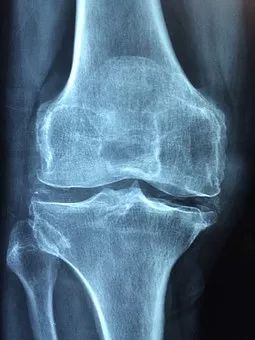

“骨刺”也叫骨质增生,而在医学中其真正的术语是“骨疣”,这是关节因种种原因造成软骨的磨损、破坏,并促成骨头本身的修补、硬化与增生。

左侧:健康的膝关节,右侧:存在软骨磨损、骨刺、关节退行性变的膝关节